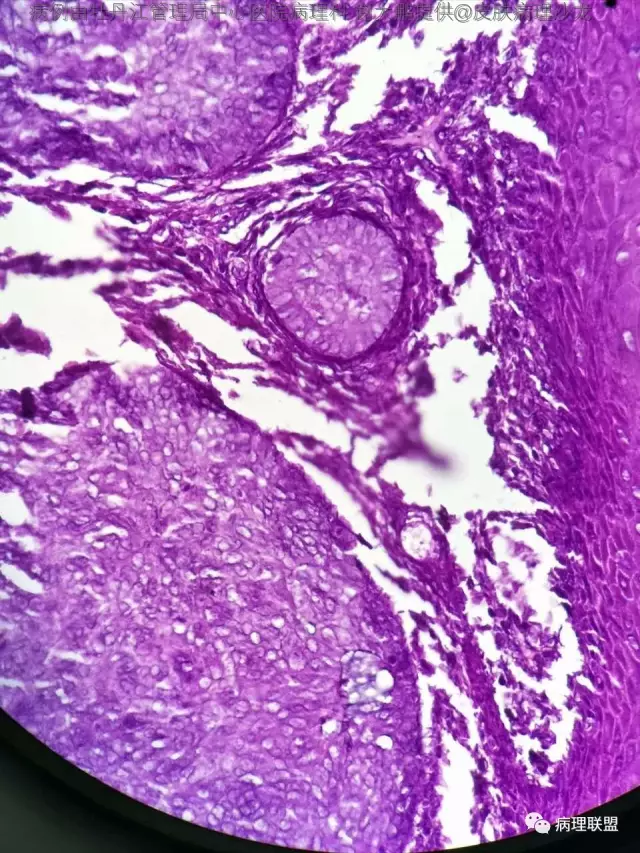

69岁,鼻翼肿物2年,1.5厘米大小,麻烦老师们帮忙看看,谢谢(病例由牡丹江管理局中心医院病理科 谢大鹏提供,致谢!)